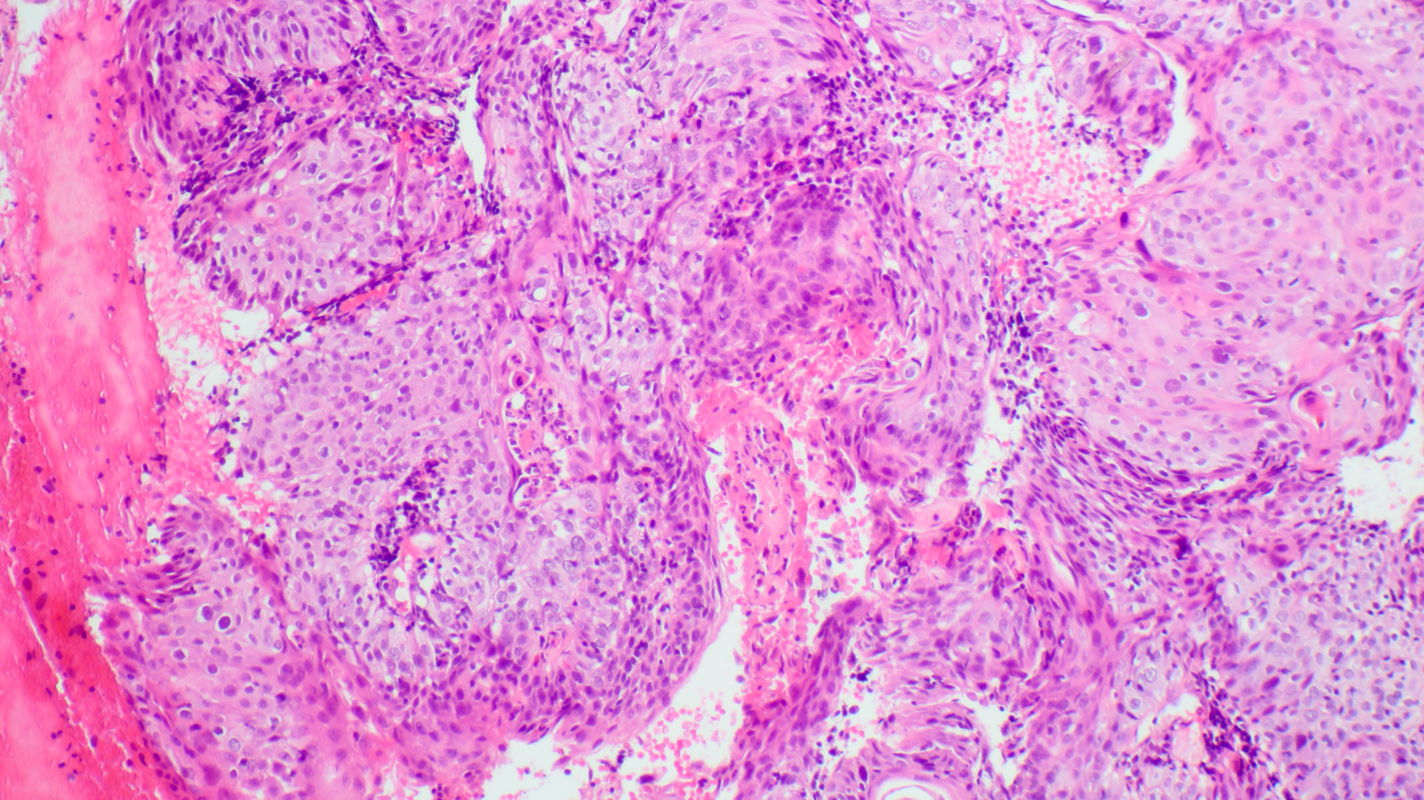

H&E stain of tissue sampled at 12 o’clock by punch biopsy shows aggregates of highly atypical squamous cells with malignancy criteria of anisonucleosis, hyperchromasia, altered nuclear-cytoplasmic ratio, and atypical mitoses. The histopathologic diagnosis is invasive squamous cell carcinoma G2. Laparoscopic lymph node staging classified the disease as FIGO stage IIb pN0, and the patient was treated with primary chemoradiation.